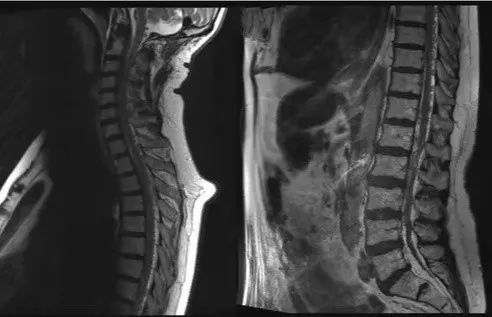

苏灿定睛一看,发现患者的脊髓mri有典型的虫蚀样血管流空影(见下图)

图片尺寸492x317